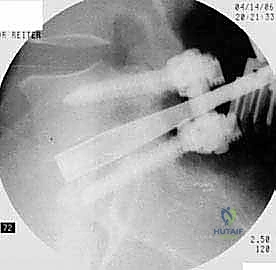

يتم وضع المريض على بطنه. يتم عمل شق جراحي دقيق في أسفل الظهر. باستخدام أجهزة الملاحة الجراحية والأشعة السينية الحية (Fluoroscopy)، يتم تحديد المستويات الفقرية المستهدفة بدقة.

الخطوة 4: زراعة القفص والطعم العظمي (Cage Insertion)

يتم إدخال قفص مصنوع من مادة PEEK أو التيتانيوم، مملوء بطعم عظمي (يؤخذ غالباً من المريض نفسه أو طعم صناعي)، في المساحة الفارغة. هذا القفص يعيد الارتفاع الطبيعي للفقرات ويخفف الضغط عن منافذ الأعصاب.

| عدد الأقفاص (Cages) | يتم وضع قفصين (واحد في كل جانب). | يتم وضع قفص واحد كبير مائل. |